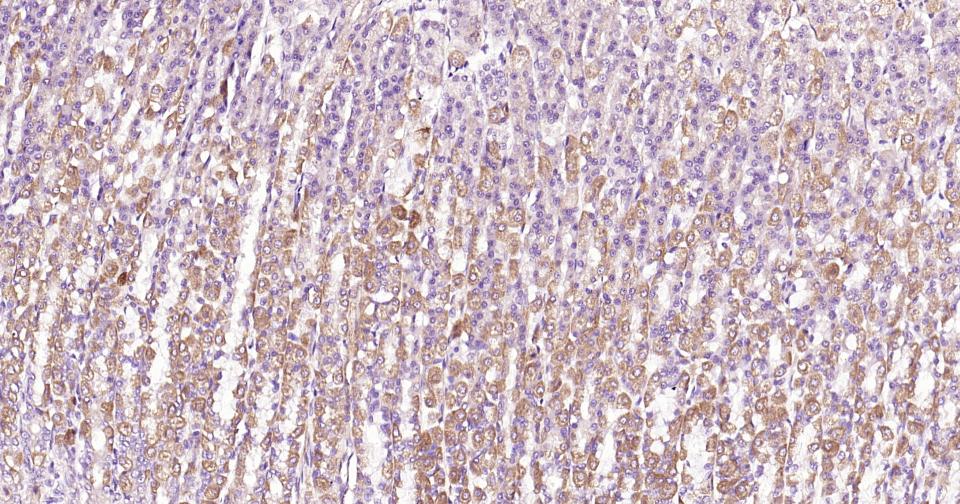

Paraformaldehyde-fixed, paraffin embedded Mouse Stomach; Antigen retrieval by boiling in sodium citrate buffer (pH6.0) for 15 min; Antibody incubation with Beclin 1 Monoclonal Antibody, Unconjugated(bsm-61085R) at 1:200 overnight at 4°C, followed by conjugation to the bs-0295G-HRP and DAB (C-0010) staining.

Paraformaldehyde-fixed, paraffin embedded Mouse Kidney; Antigen retrieval by boiling in sodium citrate buffer (pH6.0) for 15 min; Antibody incubation with Beclin 1 Monoclonal Antibody, Unconjugated(bsm-61085R) at 1:200 overnight at 4°C, followed by conjugation to the bs-0295G-HRP and DAB (C-0010) staining.

Paraformaldehyde-fixed, paraffin embedded Human Colon; Antigen retrieval by boiling in sodium citrate buffer (pH6.0) for 15 min; Antibody incubation with Beclin 1 Monoclonal Antibody, Unconjugated(bsm-61085R) at 1:200 overnight at 4°C, followed by conjugation to the bs-0295G-HRP and DAB (C-0010) staining.

Paraformaldehyde-fixed, paraffin embedded Human Kidney; Antigen retrieval by boiling in sodium citrate buffer (pH6.0) for 15 min; Antibody incubation with Beclin 1 Monoclonal Antibody, Unconjugated(bsm-61085R) at 1:200 overnight at 4°C, followed by conjugation to the bs-0295G-HRP and DAB (C-0010) staining.